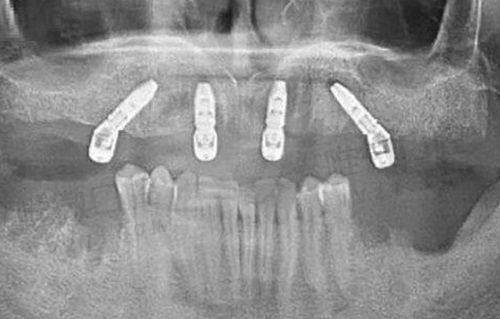

别看是连锁机构,格伦菲尔口腔在设备上的投入可是一点不含糊。医院引进了不少国内外上高端的牙科设备,比如德国的ICX种植导航系统、瑞士士卓曼口扫仪、数字化CBCT影像系统等等。其中数字导航种植技术,可以将误差降低至0.1毫米,让种牙更精细、更微创,修复也更快。